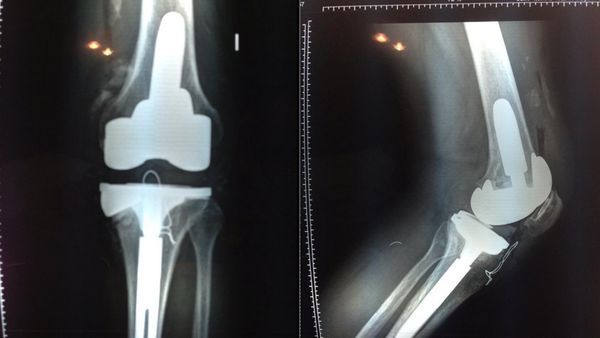

Radiografía de la rodilla de Ricardo Fort

En noviembre del 2013 Ricardo regresó de Miami con un objetivo claro: terminar de una vez por todas con sus problemas de salud y los dolores que lo aquejaban. Fue por eso que se internó en la Trinidad, y convocó a una junta médica para determinar de qué manera podía tratarse su rodilla, tras seis operaciones.

Su situación era tan extrema que tras fracturarse el fémur en el país del norte, arribó al aeropuerto en silla de ruedas: "El vuelo fue complicado. Me medicaron para poder viajar. Los dolores son insoportables, no hay medicamento que me pueda sacar el dolor. La rodilla quedó mal operada y ahora vamos a hacer una junta médica para ver qué se puede hacer porque eso me trae problemas en la columna y tengo el cuello rectificado. Hay médicos que me arruinaron la vida", se lamentaba.

En abril de ese año fue operado de esa maldita rodilla: "Fue doloroso, la verdad. Gracias a los calmantes puedo aguantar el dolor y mañana empezaremos con la kinesiología para empezar a mover la pierna y caminar de a poco con muletas", relató Fort al día siguiente del procedimiento quirúrgico.